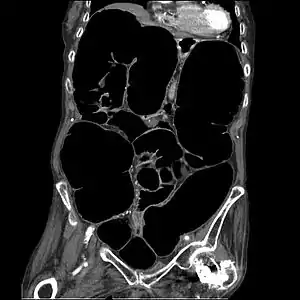

CT-Scan showing a coronal section of the abdomen of an elderly woman with Ogilvie syndrome

Acute colonic pseudo-obstruction is characterized by massive dilatation of the cecum (diameter > 10 cm) and right colon on abdominal X-ray.[2][3] It is a type of megacolon, sometimes referred to as "acute megacolon," to distinguish it from toxic megacolon.